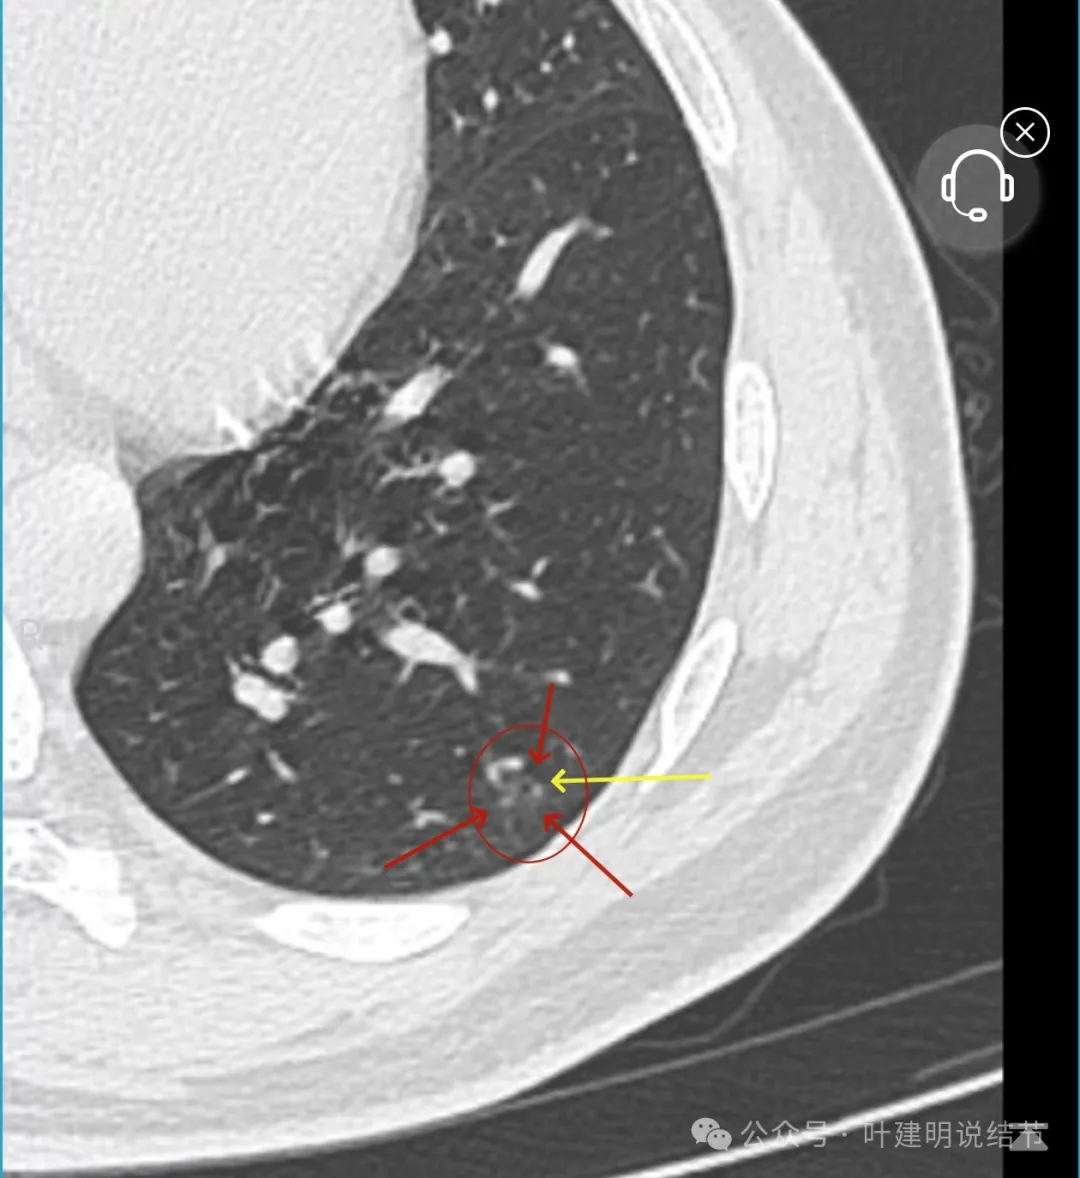

左下叶结节,轮廓稍显模糊,邻近有血管走行,无血管弯征,病灶中间密度稍低,结节密度很淡,仅小片状模糊影似的。

右上叶与左下叶这两处结节均密度很低,非常淡,而且瘤肺边界并不是特别清晰,考虑少许肺泡上皮增生可能性大,目前没有什么风险,可常规年度复查随访。不能太着急,也不必太着急干预处理。我一直强调不要管最后病理是什么,而是从影像上判断风险如何、纯不纯,密度高不高,还能不能观察。你这种不单密度低,还小,不需要过分担心的,安心随访便可。意见供参考!

当地说考虑微浸润性腺癌的左下主病灶影像连续层面展示:

病灶出现,显模糊。

上图层面轮廓较清,但密度很淡,似见血管走行,但靠左前方的似条状磨玻璃密度与血管连着的到底是血管分支还是结节的一部分,其实并不确切。如果其实是血管分支,那病灶与它之间就不是空泡。

病灶在此层整体边缘显糊,灶内有空泡似的,瘤肺边界欠清。

边缘不平,还是灶内多发小空泡?邻近血管与之紧贴,但血管无异常走行。病灶密度很低,显糊。

中间所谓空泡更像是细支气管扩张,内壁非常光滑且圆形。

病灶边缘区淡而模糊。

某省胸科医院医生会诊后给出的意见是:左下肺后基底段(结节)达Lung-rads4B类,微浸润性腺癌可能,建议手术干预。签名的是B医生,后面给出了周一A主任肺结节门诊,周四B主任门诊。大概是团队成员,A医生是著名大咖,B医生是团队骨干成员!

这个病灶会是微浸润性腺癌吗?当然没有病理诊断,我也不能说百分之百必不会,但这样的病灶已经风险大到必得尽快手术切除干预了吗?显然还早着呢:1、影像不是典型的结节状;2、边缘与轮廓模糊不清;3、灶内似有细支气管扩张(更容易是细支气管扩张伴少许周围炎或肺泡上皮增生);4、血管邻近走但无牵拉影响;5、没有实性成分,没有锐利毛刺,没有胸膜牵拉,没有血管进入,没有任何倾向风险性高的影像特点。我一直强调:肺结节是否要干预处理,不要纠结于最后病理是什么,而要看风险高低;而风险高低的最重要术前判断依据一是随访有无进展,二是有没有实性成分。只要没有肉眼可见的影像上的实性成分,风险就是低的!何况病理也是人看的,原位还是微浸润,不典型增生还是原位有时也在一念之间。